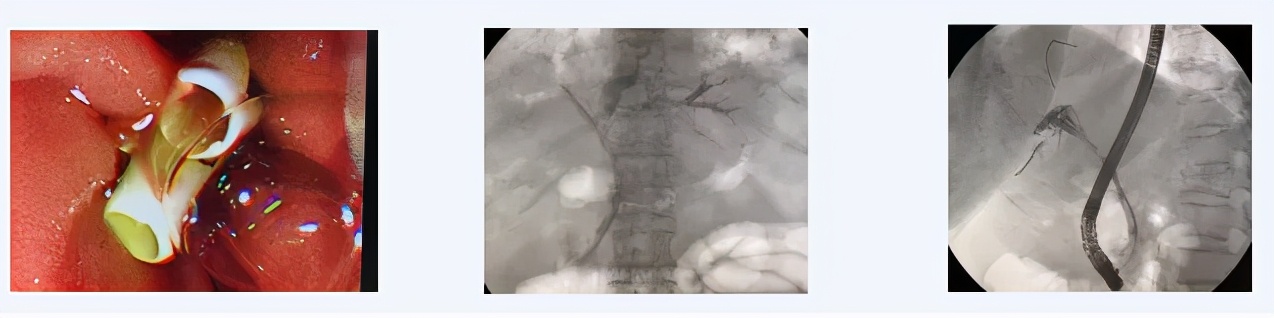

患者89岁,男性,因“梗阻性黄疸,肝门部胆管占位,胆总管狭窄”由老年病科转至西青医院普通外科病区完善相关检查,考虑肝门部恶性肿瘤。主治医师王金伟主持病例讨论中提到,考虑到患者高龄,基础疾病较多,无法耐受手术治疗,而患者如无法解除梗阻状态,病情可能进一步发展并危及生命。在权衡患者情况后,通过与患者及家属沟通,选择ERCP进行针对性微创化治疗方案。遂后,在天津市南开医院内镜专家的指导下,王金伟医生联合内镜室护理团队在介入室局麻下,通过十二指肠镜成功为该高龄患者放置两根胆道支架达左右肝管引流肿瘤上段胆汁改善肝功能,这将为延续患者生命发挥重要作用,患者术后好转出院。